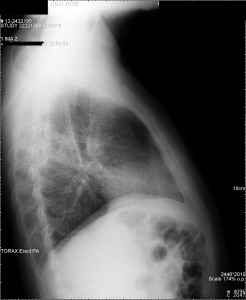

La radiografia de tórax posteroanterior (PA) y lateral(L) es una herramienta fundamental en la detección y diagnóstico de enfermedades en el tórax y continúa siendo utilizada en la evaluación inicial del paciente. Nunca hay que mirar solo la PA, porque en esta hasta un 25% del parénquima pulmonar está oculto por el mediastino, la silueta cardiovascular y los diafragmas por lo que hay veces que la anormalidad puede ser detectada únicamente en la RL.

Haz click en las imágenes para verlas ampliadas